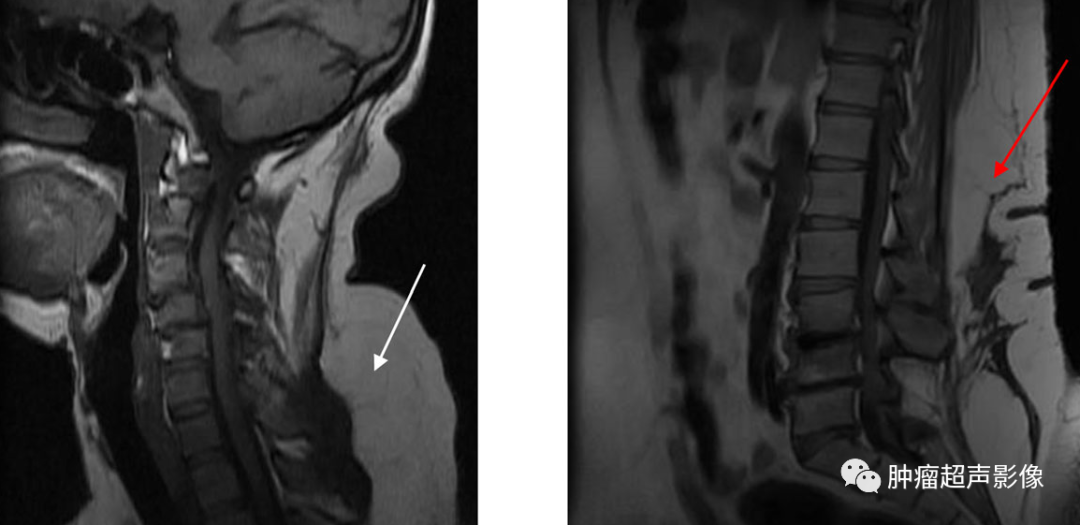

马德龙综合征[s0]image.png[s1]哈医大四院颈部长了大肉球当心患上罕见病马德龙病[s2]马德龙病[s3]济南市传染病医院医生让你了解马德龙病[s4]马德龙综合征 baijiahao.baidu.com[s5]成都男子身患罕见马德龙病,全球仅约400例![s6]马德龙综合征 来自网易[s7]【哈医大四院】酗酒患上马德龙病 医生巧妙切除颈部肿瘤[s8]马德龙综合征 来自搜狐网[s9]2.多发性对称性脂肪增多症(madelung病)[s10]马德龙综合征 来自搜狐网[s11]马德龙综合征[s12]byb.cn[s13]【超声角】★对称分布の浅表肿物★【附两例病例】★马德龙综合征★[s14]肘部对称性包块罕见部位的马德龙病[s15]马德龙综合征 baijiahao.baidu.com[s16]马德龙综合征 来自网易[s17]马德龙综合征ppt课件[s18]陪拉格氏病[s19]下和非内镜下面部、颈部手术治疗各类疤痕、以及自体脂肪移植技术等。 手术治疗良性对称性脂肪瘤病(马德龙病)疗效好耳鼻咽喉头颈外科[s20]马德龙综合征:当饮酒成为健康的隐形杀手[s21]直到几年前,与她一样有着同样体型特征的弟弟因发病被查出患有马凡综合[s22]手术方法,保留颈部肌肉和器官,沿颈筋膜彻底切除增生脂肪,避免复发。马德龙病,良性对称性脂肪瘤病(be[s23]马德龙综合征 凤凰网[s24]image.png[s25]马德龙综合征 新浪网[s26]什么是马德龙病![s27]马方综合征躯干症状图[s28]【超声随响】第07期 马德龙综合征 madelung syndrome[s29]马德龙病又叫多发性对称性脂肪增多症,是一种罕见病,多发于中年男性。可以导致酒精在肝脏中的代谢出现紊乱[s30]假性马德隆(madelung)畸形一例[s31]什么是马德龙病[s32]马德龙综合征 baijiahao.baidu.com[s33]【讨论】马德隆畸形[s34]马德隆氏畸形x表现课件[s35]嗜酒如命患上罕见马德龙病,医生从大爷颈部取出大团肿瘤[s36]典型病例marshallwhite综合征[s37]马德龙病的超声表现[s38]马方综合征[s39]